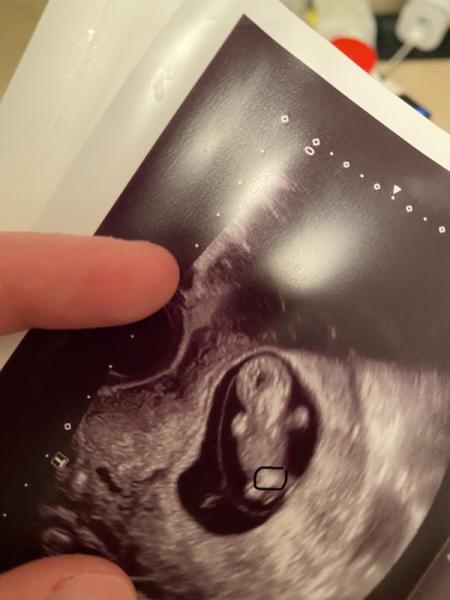

hey Leute , mich würde euch gerne mal nach eurer Meinung fragen natürlich weiß ich das ihr keine Ärzte seit und man das Geschlecht so früh schwer erkennen kann ! ich möchte nur eure Meinung wissen vlli gibt es unter euch mommys ein paar die Erfahrungen damit haben :) undzwar habe ich dieses Ultraschall Bild in der 11 ssw bekommen und ich hatte das Gefühl das meine Ärztin mit Absicht so das Kind fotografiert hat um mir was zu sagen . meine Frage wäre : kan man an diesem kleinen eingekreiste Punkt erkennen das es „VIELLEICHT „ ein Junge werden könnte??? Ich bin jetzt in der 13 ssw also noch 1 Woche warten aber ich bin einfach so aufgeregt was es wird .

Bild zu 11 ssw Geschlecht erkennen? - Schwanger - wer noch? Rund um die Schwangerschaft